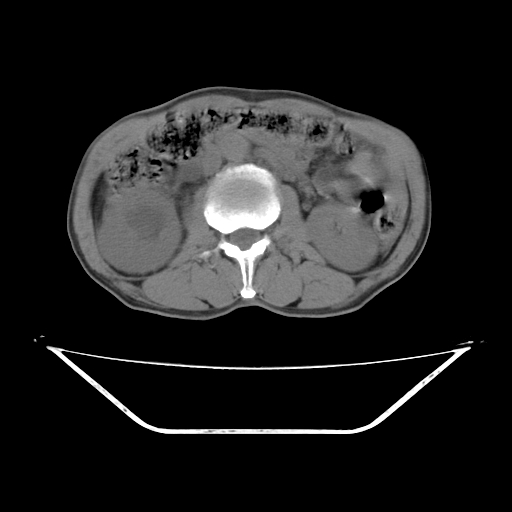

平扫

考虑右肾盂癌,肾动脉受侵,右肾功能减退,右肾盂输尿管积水,管壁增厚,考虑种植转移,应该把下面扫完的

支持右侧肾盂癌伴肾静脉瘤栓形成可能性大,右肾结石.肝右叶后段低密度影,不除外转移.

考虑右肾盂癌,肾动脉受侵,右肾功能减退,右肾盂输尿管积水,管壁增厚,考虑种植转移  支持

右肾囊实性占位,支持肾癌,窗宽窗位不是很理想

右肾盂旁ca并肾静脉瘤栓形成/肾功能降低。

右肾结石。

右肾盂癌,肾动脉受侵,右肾盂输尿管积水,管壁增厚,考虑种植转移

支持 右侧肾盂癌伴肾静脉瘤栓形成可能性大,右肾结石;肝右叶后段低密度影,不除外转移。

1.右侧肾盂癌伴肾盂积水。

2.肾脏功能减退,原因有:(1)肾动脉受侵。(2)肾静脉受侵(3)肾积水,等。本例,肾动脉显影较好,但受压明显;肾静脉无明显显示,受压或静脉癌栓,下腔静脉腔内未见明显充盈缺损。

3.右侧上段输尿管扩张,原因:(1)积水所致;(2)种植。